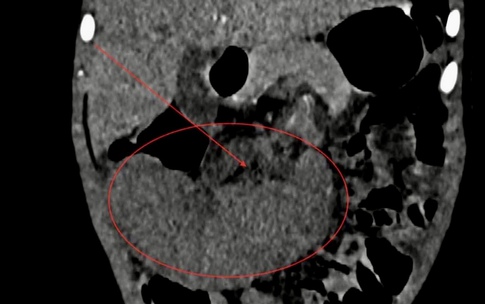

Camera bệnh viện - 10/10/2025 14:55SKĐS - Việt kiều Mỹ 73 tuổi quyết định đến Bệnh viện Đa khoa Thủ Đức để thăm khám sau khi xuất hiện các dấu hiệu bất thường về đường tiêu hóa. Kết quả phát hiện khối u đại tràng ác nên nhanh chóng được phẫu thuật cắt bỏ.

Việt kiều Mỹ 73 tuổi lựa chọn về Việt Nam phẫu thuật khối u đại tràng ác tính